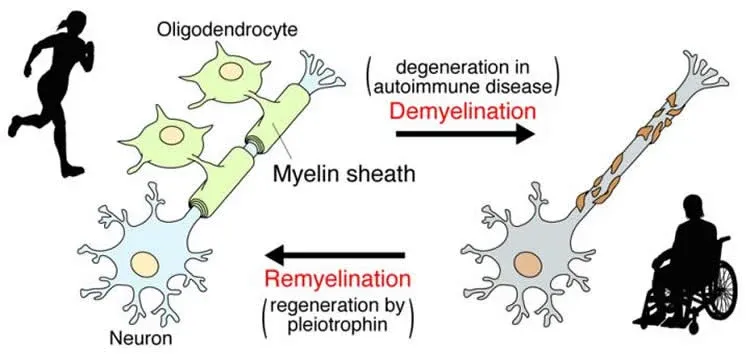

MS is an autoimmune disease that damages the myelin coating around nerve fibres, causing disruption of nerve signals

Patients with MS exhibit damaged myelin and nerve fibres (demyelination)

None of the drugs seek to repair or reverse the damage of myelin, (remyelination),which may stop progression reverse the course of MS

Demonstrated Remyelination

Loss of coating around nerve cells with degeneration

(demyelination/loss of myelin & axons)

Dioprotectrome™ treated

Repair of coating around nerve fibres

(remyelination) and neurological recovery

Repair of coating around nerve fibres(remyelination) and neurological recovery